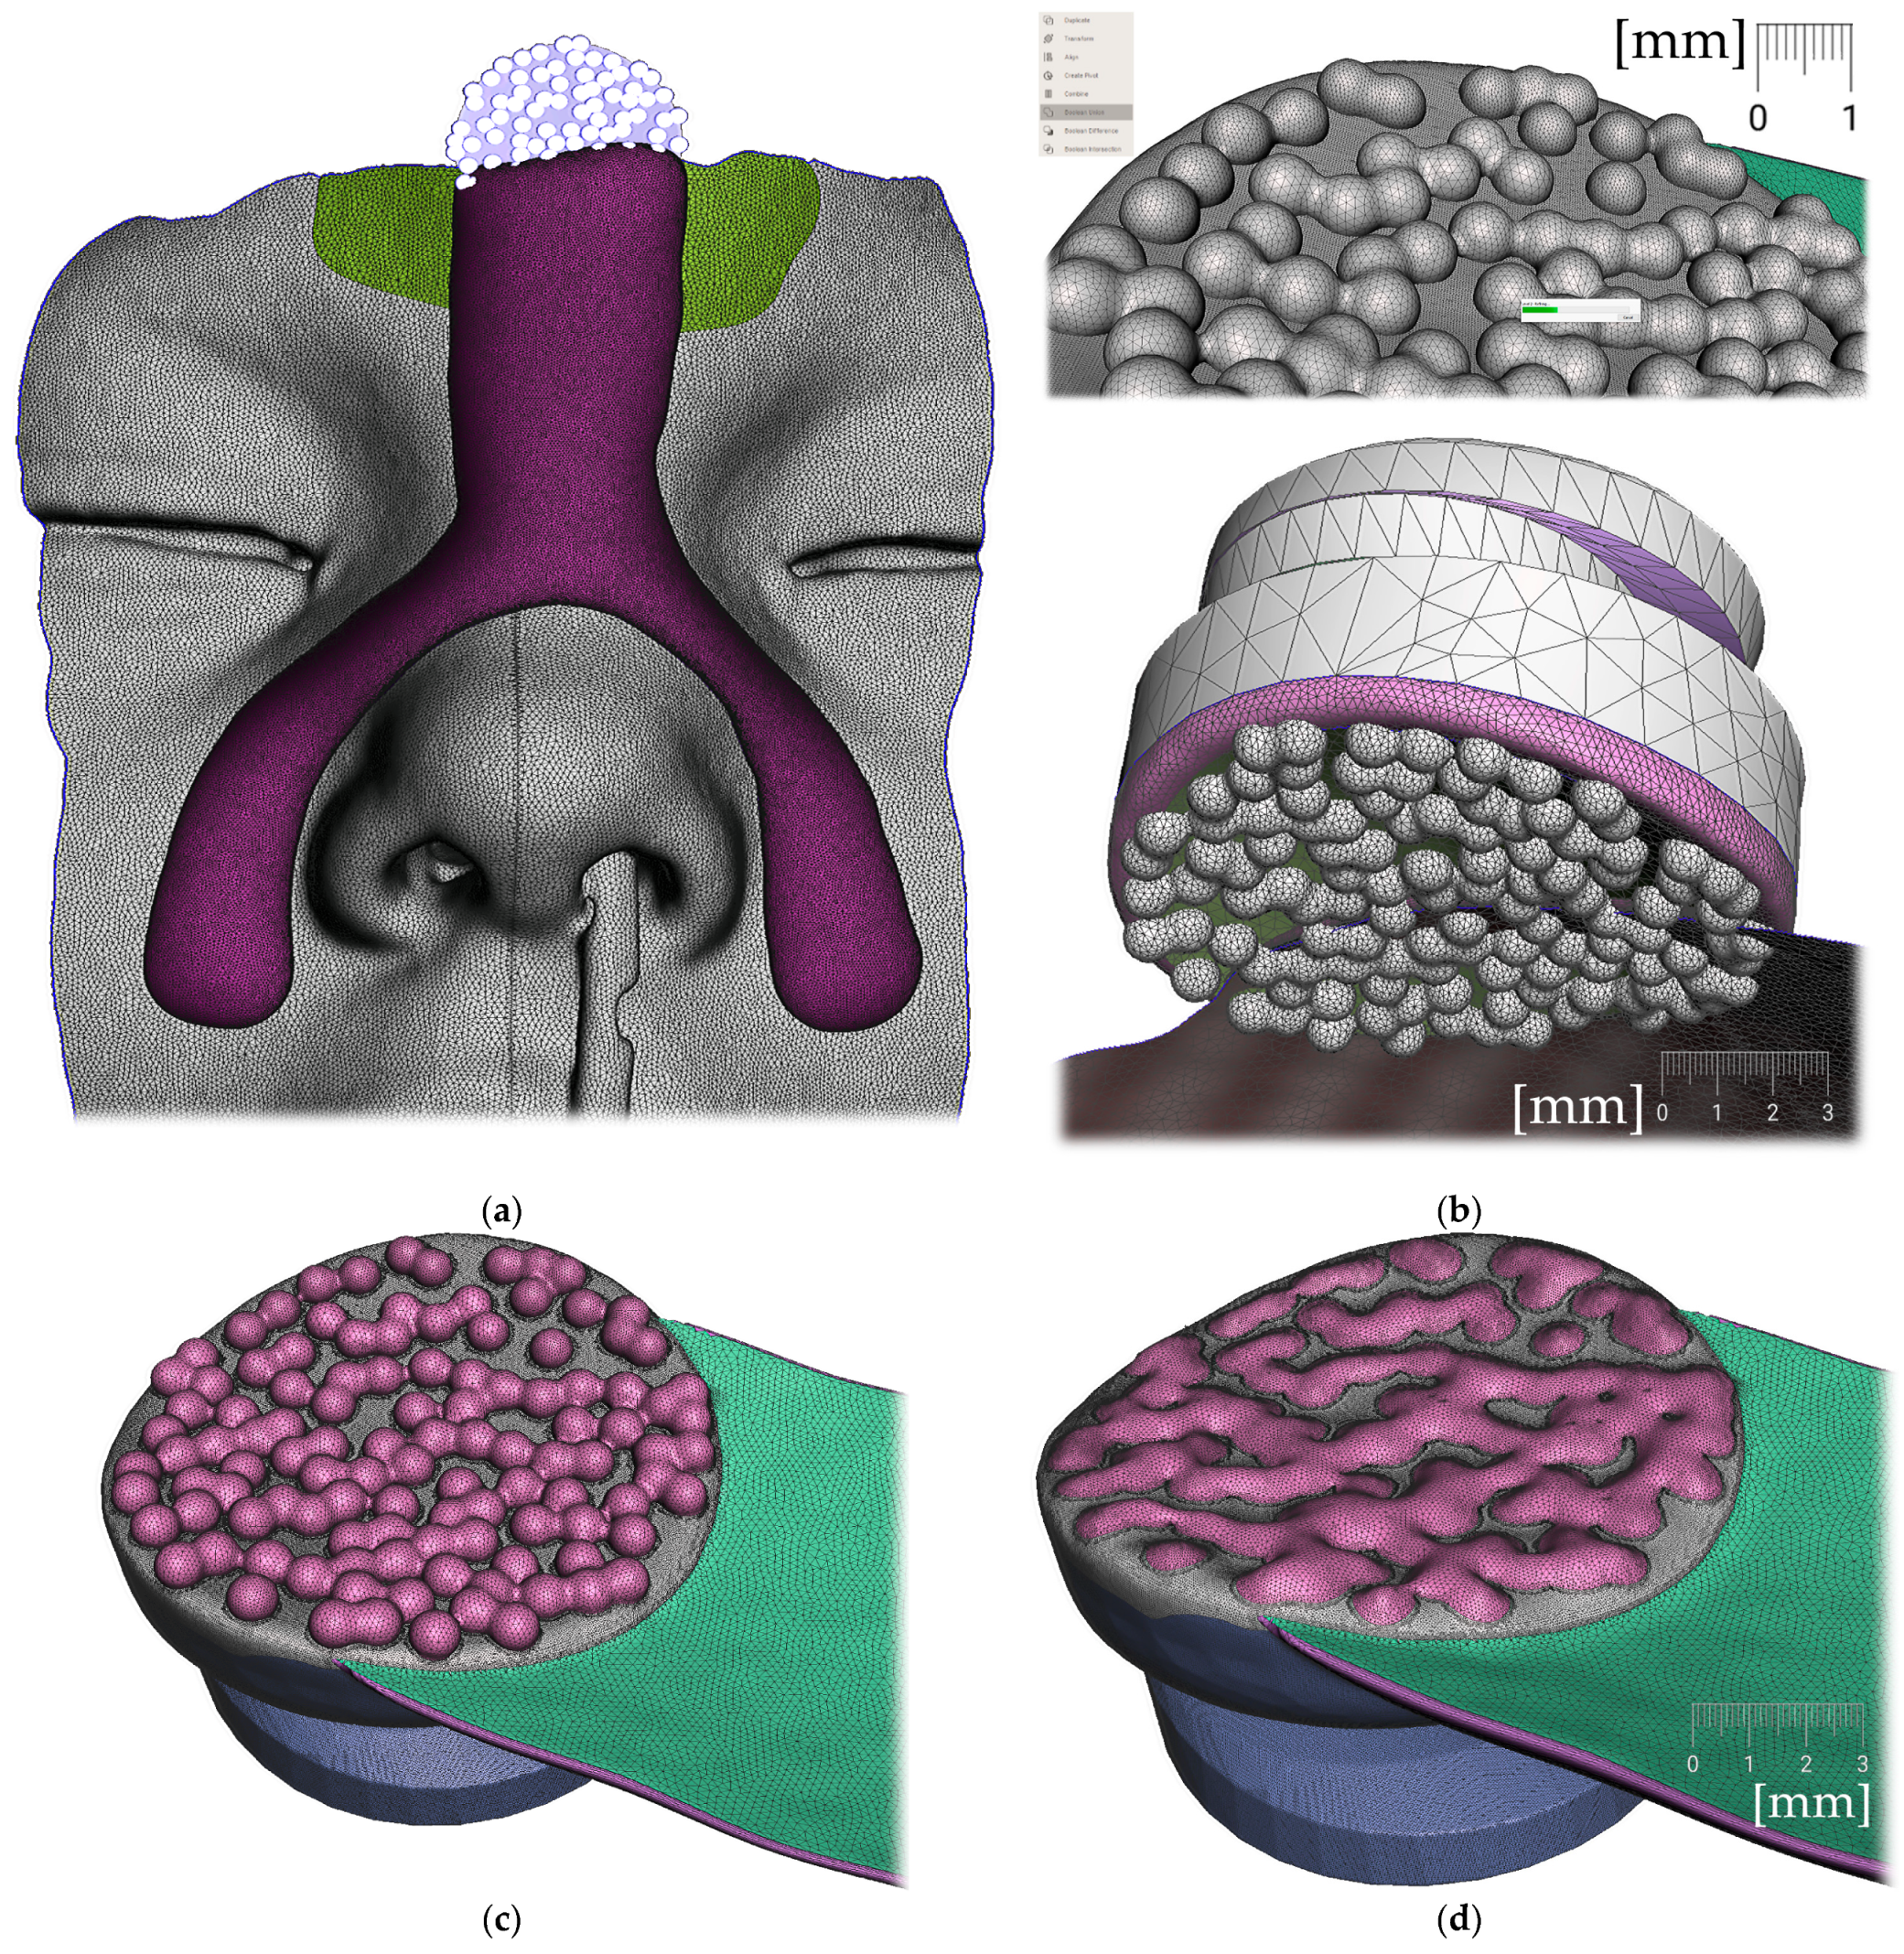

To gain 3D information from CT slices, they need to be segmented first. CT segmentation can be performed in 3D Slicer (www.slicer.org (accessed on 11 September 2022)), a free, open-source and multi-platform software package widely used for medical, biomedical, and related imaging research. The method presented in this paper used software Invivo 6 (Anatomage Inc., San Jose, CA, USA) for CT segmentation with the output in STL file format. The appliance presented in this paper had two parts, connectable with a simple click-in sphere joint:

After the 3D models alignment, the following steps shall be performed in Meshmixer to create a personalized appliance suitable for additive manufacturing:

• Alveolar part creation (the body)

• Pharyngeal part creation (the spur)

• Connecting the body and the spur (Figure 14)

All the following steps (Figure 9, Figure 10, Figure 11, Figure 12, Figure 13, Figure 14, Figure 15 and Figure 16) are performed in Meshmixer™ (Autodesk®, Inc., San Rafael, CA, USA), version 3.5.474. Separate visualized steps lead to the creation of the “Alveolar part”, “spur part” and “extraoral part”. The methodology is universal and suitable for any patient. The methodology of sequential steps creating the body complementary to the morphology of the teeth, gums and palate is repeated at the renewal of the appliance due to the patient’s growth. This set of steps is performed to recreate the actualized version of this part separately without needing to edit the remaining parts of the appliance. New morphological data are provided with a new intraoral scan.